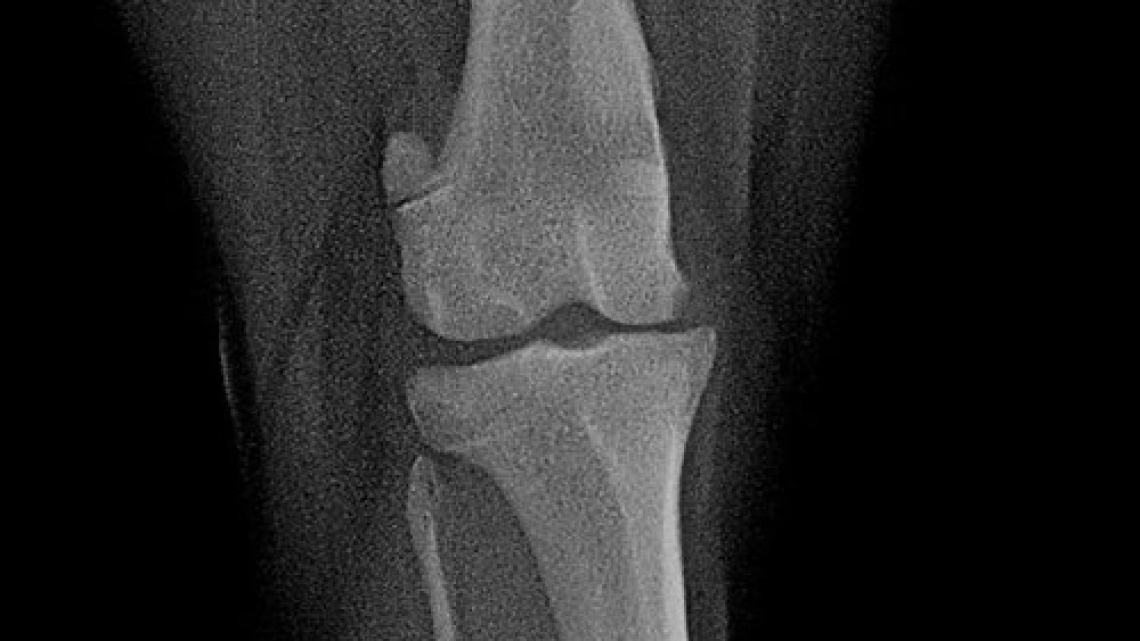

The picture shows a 2-month follow-up of the case in our previous post, with limp-free limb use and adequate bone healing.